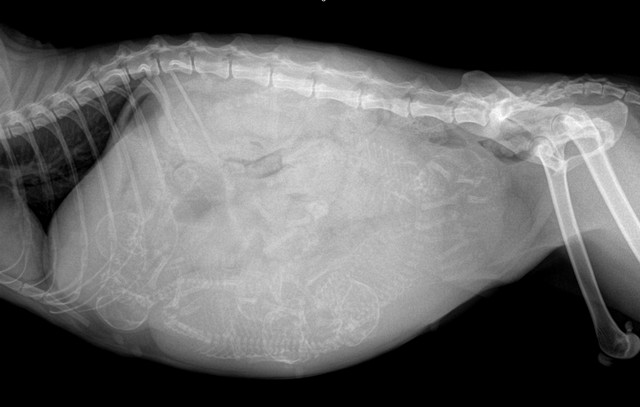

・妊娠猫をFIPによる腹水と診断

腹水や胸水があれば、腫瘍・心疾患・肝疾患・感染症・術後合併症などを除外する必要がある。血液検査、画像診断、体液の性状評価など複数の情報を総合的に判断する。

「超音波検査は何百万円もする機器です。腹水の有無だけを見る“確認装置”にしてはいけない。腹腔内臓器を丁寧に評価することが大前提です」